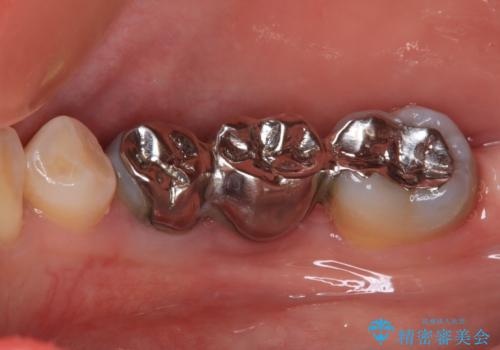

- インレーブリッジをインプラントにやり替えて銀歯を白くしたいとのことで来院された患者様です。

既に抜歯をして歯のない箇所にはインプラント治療をし、ブリッジの土台となっている歯のうち、手前側の小臼歯は既に根管治療をされている歯なのでオールセラミッククラウンへのやり替え、奥側の大臼歯はセラミックインレーへのやり替えをしていくこととしました。